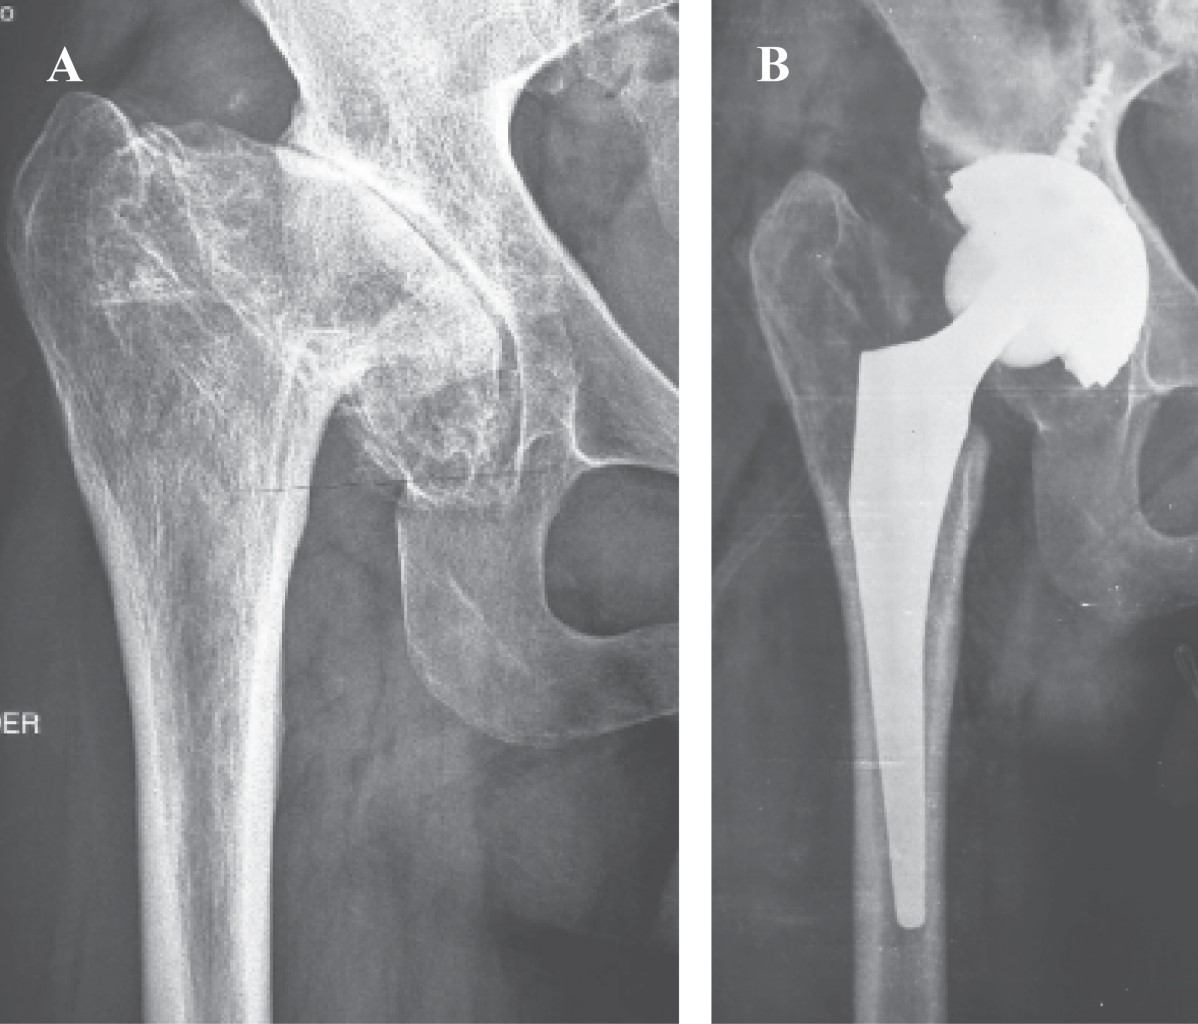

Introducción: La complicación más temida en la artroplastia de cadera después de la artritis séptica (activa o sus secuelas) es el fracaso séptico. El tratamiento en dos etapas, una vez resuelto el proceso infeccioso, es el tratamiento aceptado para la etapa aguda. El objetivo de este trabajo es establecer una pauta terapéutica para la artritis séptica en las caderas nativas, proponiendo un tratamiento en dos etapas para agudos, y un tratamiento de una etapa para las secuelas. Material y métodos: Realizamos un estudio observacional, descriptivo y retrospectivo. Analizamos a todos los pacientes que se sometieron a un reemplazo primario total de cadera en nuestra institución entre Junio de 1997 y Junio de 2016 con un diagnóstico de artritis séptica de la cadera antes de la cirugía (grupo 1: artritis séptica aguda; grupo 2: secuelas de artritis séptica). Resultados: Grupo 1: ocho caderas, con un diagnóstico agudo de artritis séptica y seguimiento de uno a seis años. Se cumplió con el tratamiento antibiótico entre la colocación del espaciador y el reemplazo protésico definitivo, y, en todos los casos, se verificó la remisión de la infección. Grupo 2: 12 caderas, El tiempo entre la infección tratada y el reemplazo de prótesis varió entre cinco y 46 años. Las cabezas femorales enviadas para cultivo eran en todos los casos negativas. Conclusiones: En los últimos 20 años, hemos obtenido resultados satisfactorios, tanto en el tratamiento de la artritis séptica aguda como en sus secuelas, interpretándolas como patologías del mismo origen pero con un tratamiento diferente. Ambos tratamientos son adecuados, siempre y cuando se respete el protocolo terapéutico establecido para cada uno de los grupos.

Figura 1